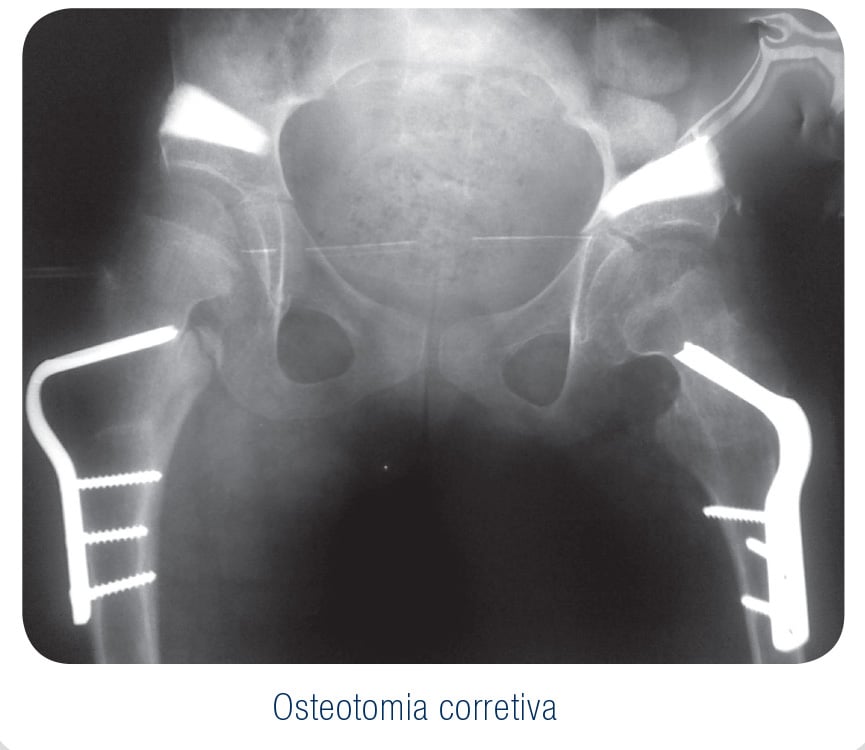

As biossoluções EincoBio para uso na Traumato-Ortopedia criaram novas alternativas com vantagens significativas, principalmente quando substituem materiais de origem orgânica, com a correta indicação naqueles procedimentos.

Com as mais variadas apresentações destes materiais fosfocálcicos, a reconstrução óssea e manutenção de espaços anatômicos, hoje tornam-se uma rotina com a aplicação dessas biossoluções.